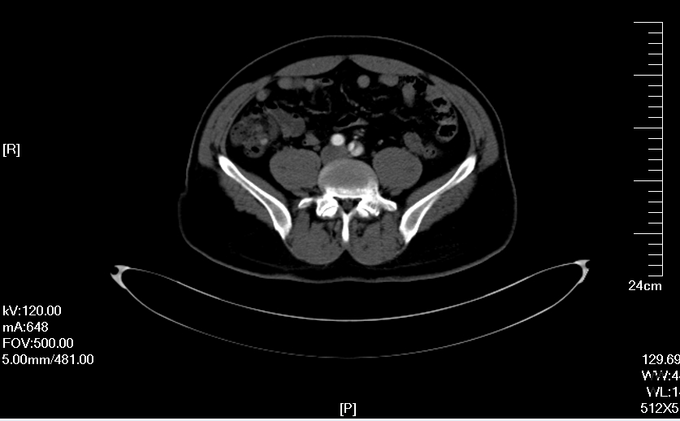

入院查体:体温36.5℃,脉搏90次/分,规则,呼吸18次/分,规则,血压150/80mmHg,胸廓正常,无胸骨叩痛。呼吸运动正常,语颤正常,无胸膜摩擦感,无皮下捻发感,叩诊正常清音,肺下界正常,双肺呼吸音粗,呼吸音对称,无罗音。心音可,心率90次/分,无杂音,腹部无压痛,无反跳痛,肝肋下未及,胆囊无压痛,Murphy征阴性,脾肋下未及,肾区无叩痛,双下肢不肿。入院后完善相关检查(胸腹主动脉CTA:主动脉夹层动脉瘤;两侧胸腔少量积液。)

予以诊断:1.主动脉夹层动脉瘤;2.高血压3级,极高危组。诊断明确后行“左颈总动脉-腋动脉转流手术+胸主动脉覆膜支架腔内隔绝术”。左侧颈部切口,游离出左侧颈总动脉,左侧锁骨下动脉,左侧椎动脉等分支。使用8mmG-tex血管一端与左锁骨下动脉行端侧吻合,G-tex血管另一端与左侧颈总动脉行端侧吻合。经右侧股动脉入路造影见主动脉夹层,破口位于左锁骨下动脉开口医院0.5cm处。左锁骨下动脉近端封闭,桥血管通畅,腋动脉及左侧椎动脉血流良好。置入美敦力胸主动脉覆膜支架(28*157mm),定位后释放。造影见胸主动脉支架释放良好。

主动脉夹层为大血管急诊,B型主动脉夹层相对预后良好。保守治疗效果尚可,近期死亡率相对不高。但对于年轻患者,我们积极治疗。患者B型主动脉夹层,破口位于锁骨下动脉附近。拟行腔内修复术。但患者破口离锁骨下动脉较近,若直接封闭,可影响左上肢活动及椎动脉顺行血流。故根据患者情况行一期复合手术(即“左颈总动脉-腋动脉转流手术+胸主动脉覆膜支架腔内隔绝术”)。术后复查可及左侧锁骨下动脉通畅,血流灌注可。可及假腔内明显血栓化。